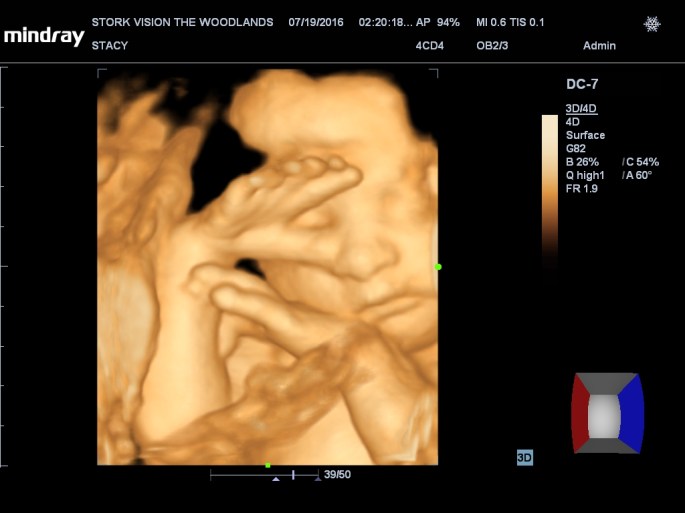

Best moment the week: Seeing Juliette on the 3D/4D ultrasound. So amazing!